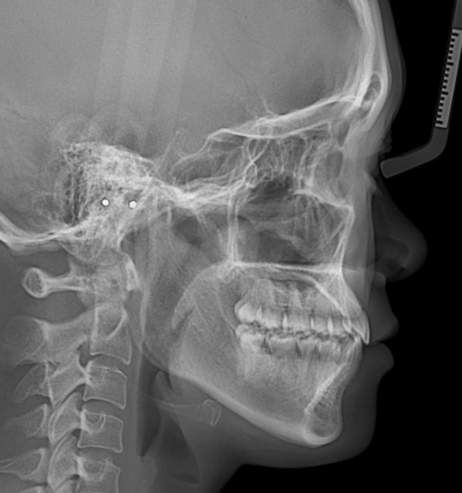

牙齿矫正后,女生的鼻、唇、颏、面部的状态恢复美观协调,面中凹陷问题得到改善,牙齿排列整齐,覆合覆盖正常,咬合良好,想要的笑线也做好了。